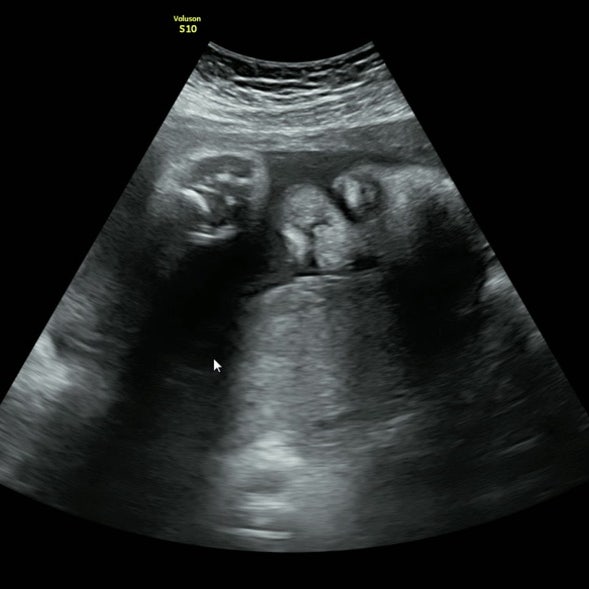

22주~29주 임신일기 성별확정,임당검사,빈혈검사,입체초음파는패스,백일해주사접종

25주차 5일에 뒤늦게 아기 성별 안 사람 나야나ㅠㅠㅠ 32주 이후 태아성별고지 위헌판정 때문일까? " ...